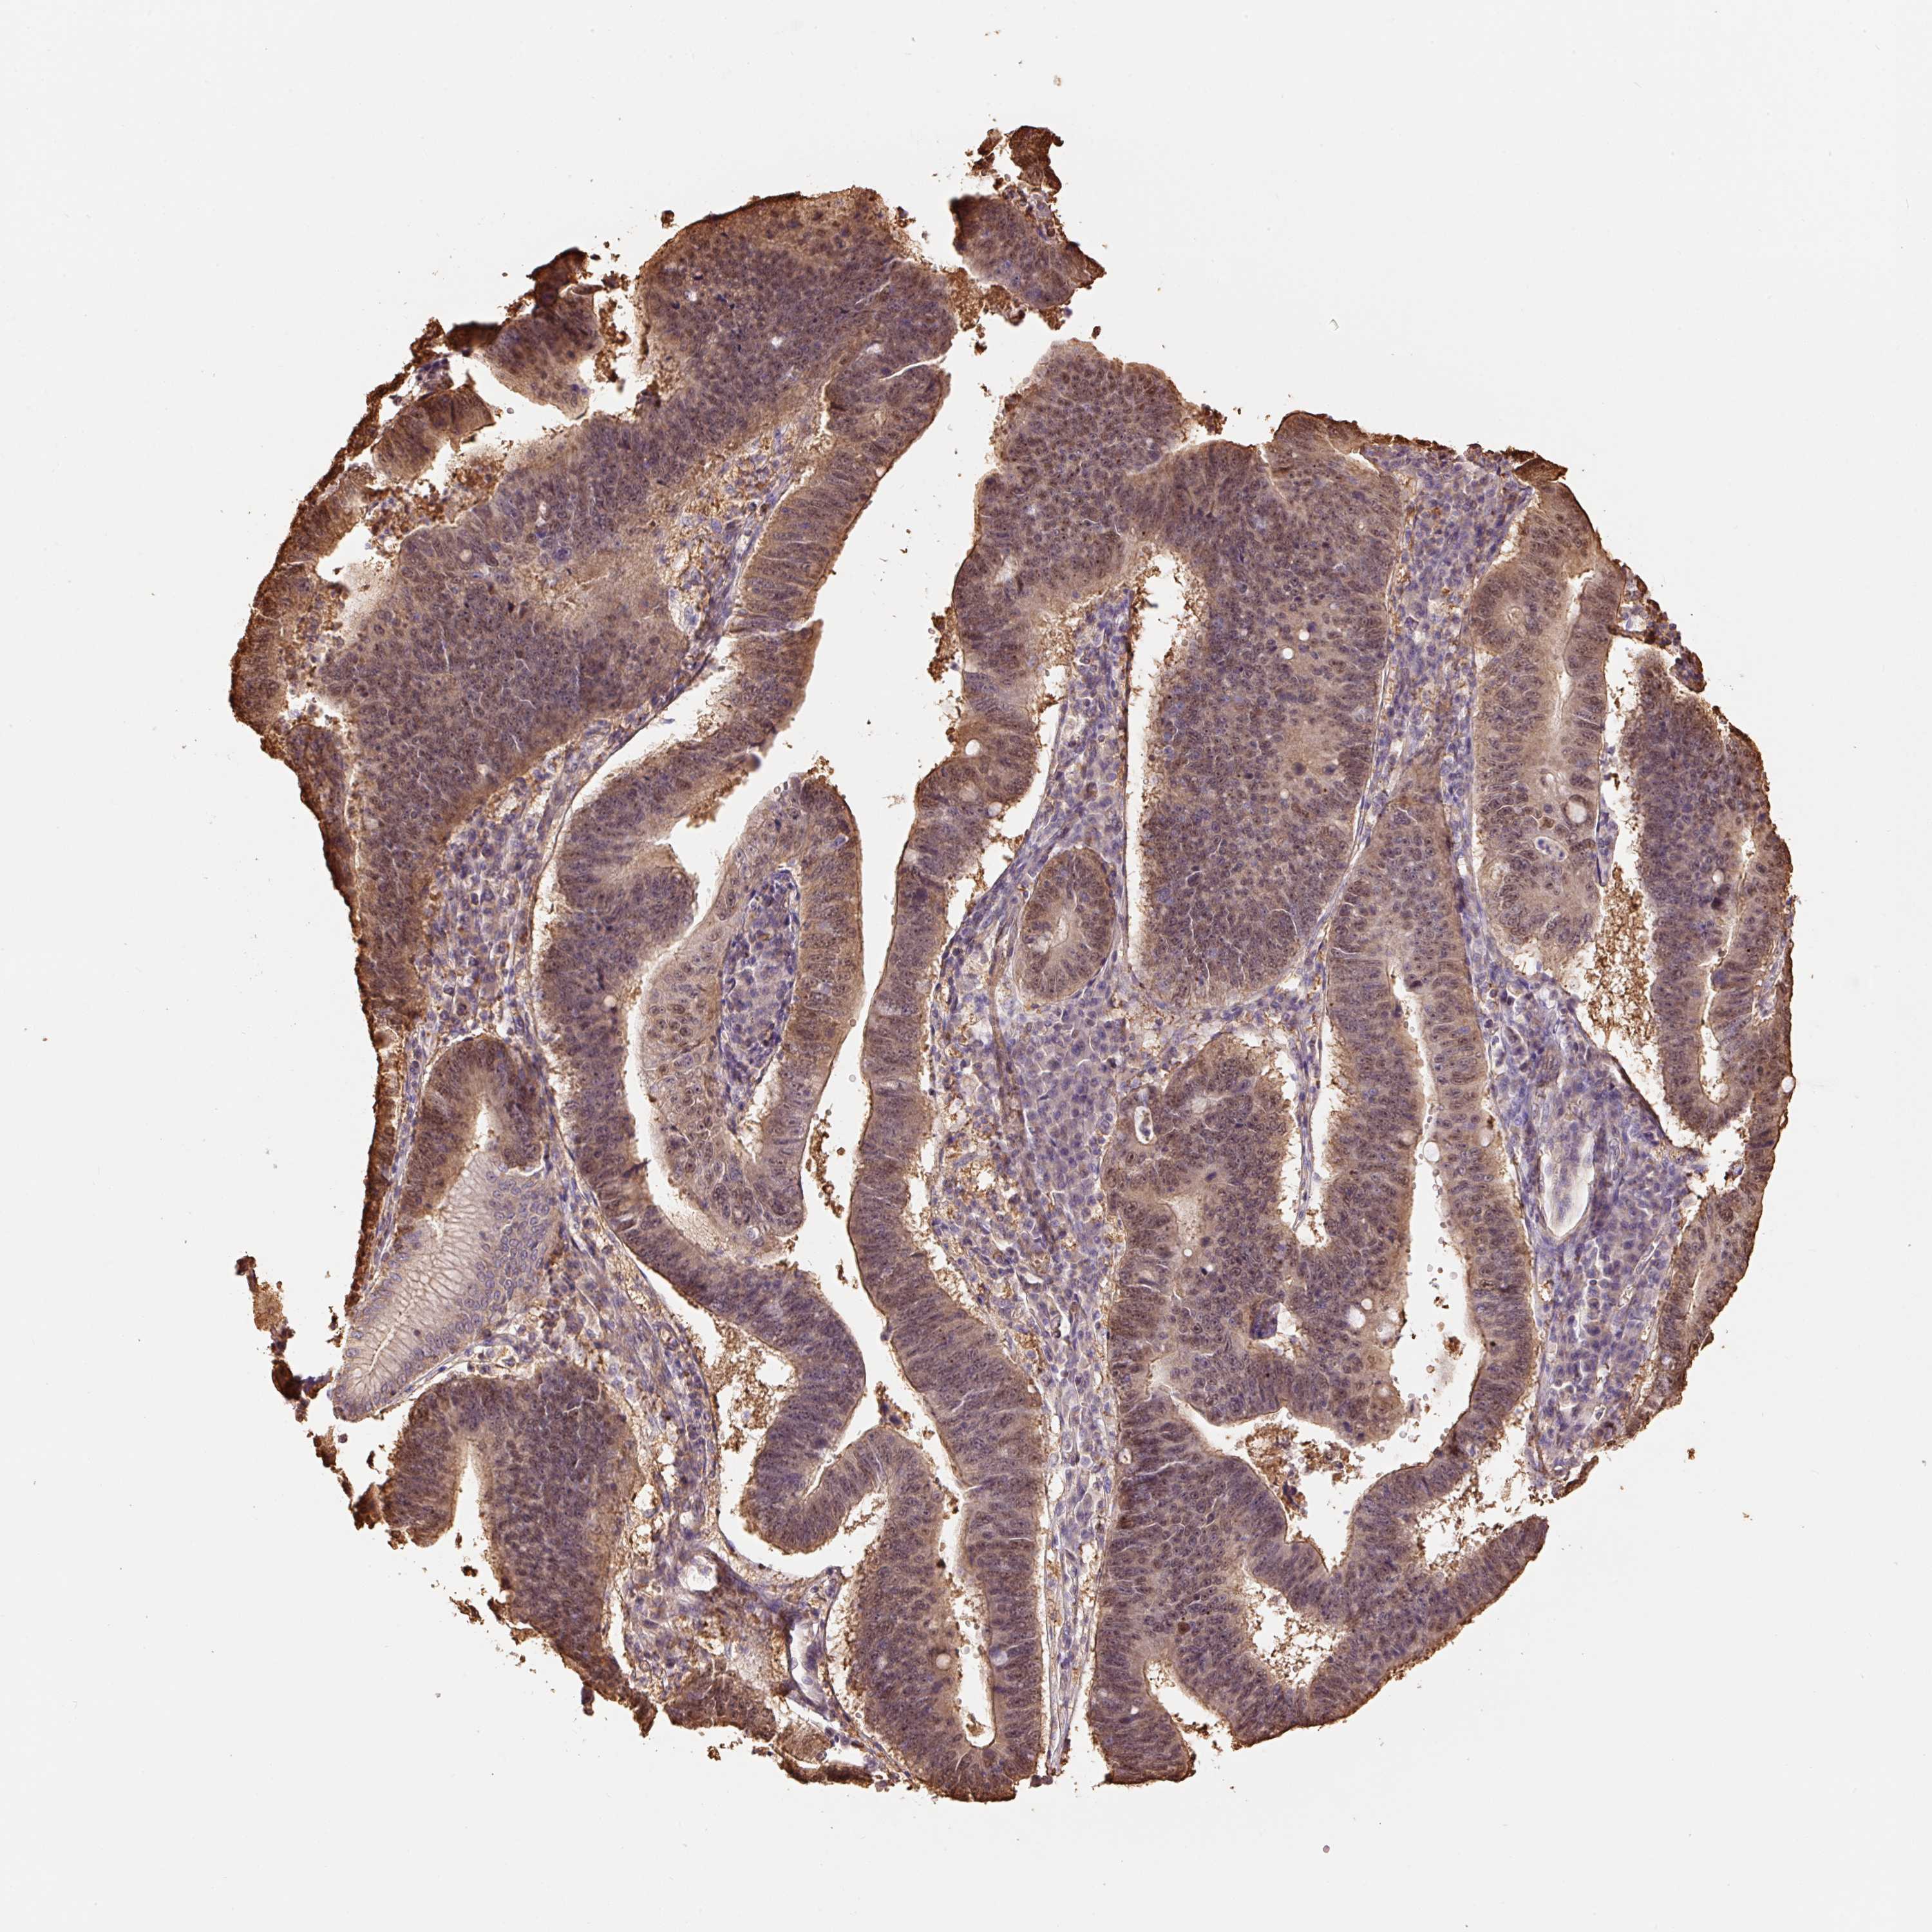

STOMACH CANCER - Protein expressioni

A mouse-over function shows sample information and annotation data. Click on an image to view it in a full screen mode. Samples can be filtered based on level of antibody staining by selecting one or several of the following categories: high, medium, low and not detected. The assay and annotation is described here.

Note that samples used for immunohistochemistry by the Human Protein Atlas do not correspond to samples in the TCGA dataset.

Antibody stainingi

Antibody staining in the annotated cell types in the current human tissue is reported as not detected, low, medium, or high, based on conventional immunohistochemistry profiling in selected tissues. This score is based on the combination of the staining intensity and fraction of stained cells.

Each image is clickable and will lead to virtual microscopy that enables deeper exploration of all samples and also displays staining intensity scores, fraction scores and subcellular localization as well as patient and tissue information for each sample.

Antibody HPA048630

Antibody HPA061142

Antibody CAB004026

Staining

High

Medium

Low

Not detected

Intensity

Strong

Moderate

Weak

Negative

Quantity

>75%

75%-25%

<25%

None

Location

Nuclear

Cytoplasmic/membranous

Cytoplasmic/membranous,nuclear

Adenocarcinoma, NOS

Adenocarcinoma, High grade